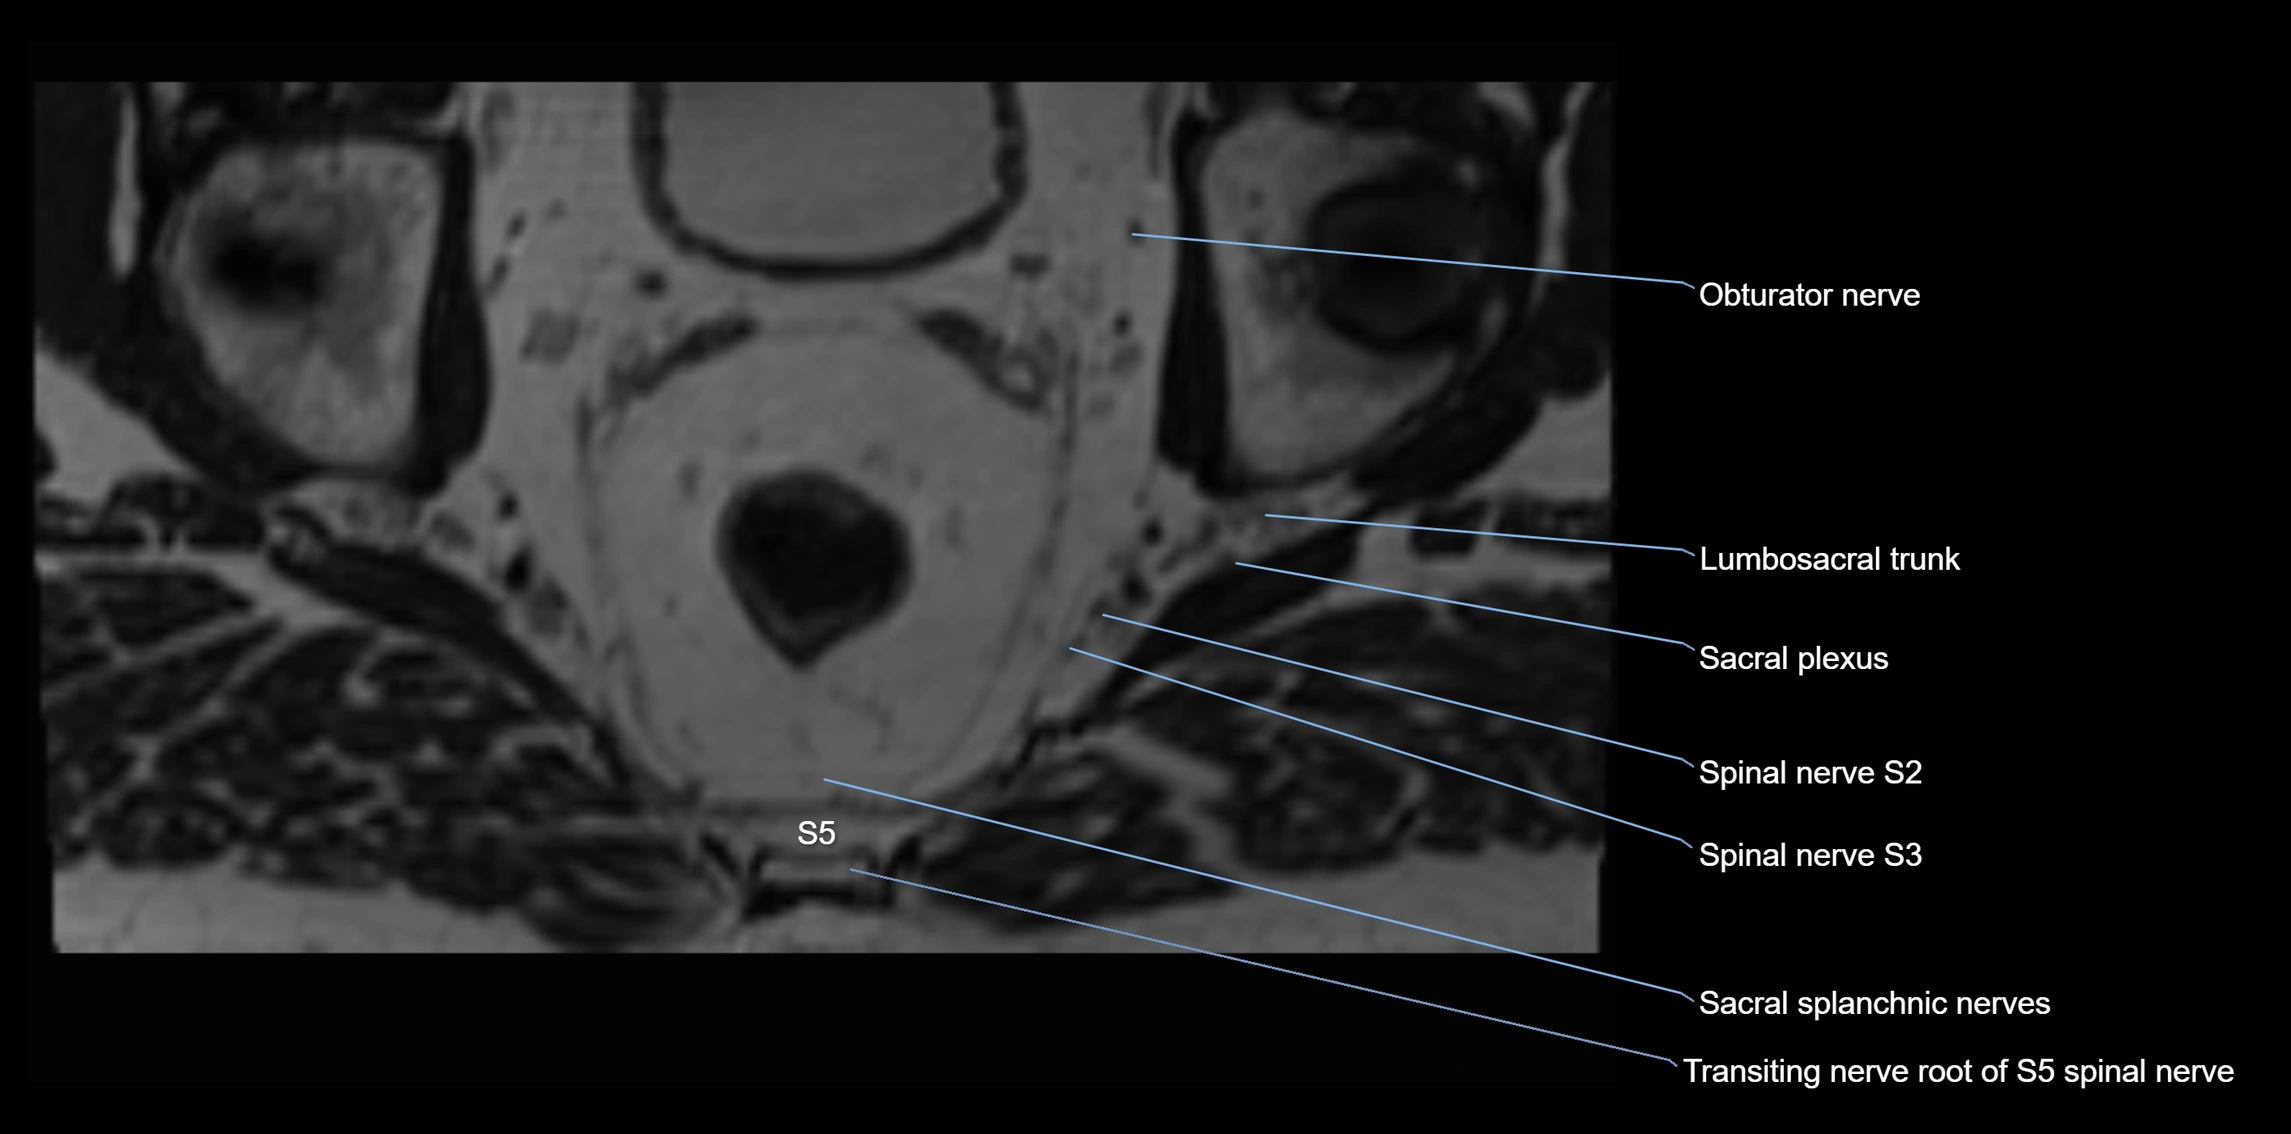

MRI Appearance

T1-weighted images:

• Nerve appears as a very thin low-to-intermediate signal intensity structure

• Surrounded by bright fat, aiding visualization

T2-weighted images:

• Nerve shows intermediate to mildly hyperintense signal compared to muscle

• Pathological involvement appears brighter

STIR (Short Tau Inversion Recovery):

• Normal nerve appears dark

• Inflamed or entrapped nerve appears bright hyperintense

T1 Fat-Sat Post-Contrast:

• Normal nerve enhances minimally

• Pathologic nerve (neuritis, entrapment, tumor infiltration) shows focal or diffuse enhancement

3D T2 SPACE / CISS:

• Nerve appears intermediate to mildly hyperintense compared to muscle

• Surrounded by bright fat or CSF, improving visualization

• Best sequence for mapping small pelvic nerves such as the anococcygeal